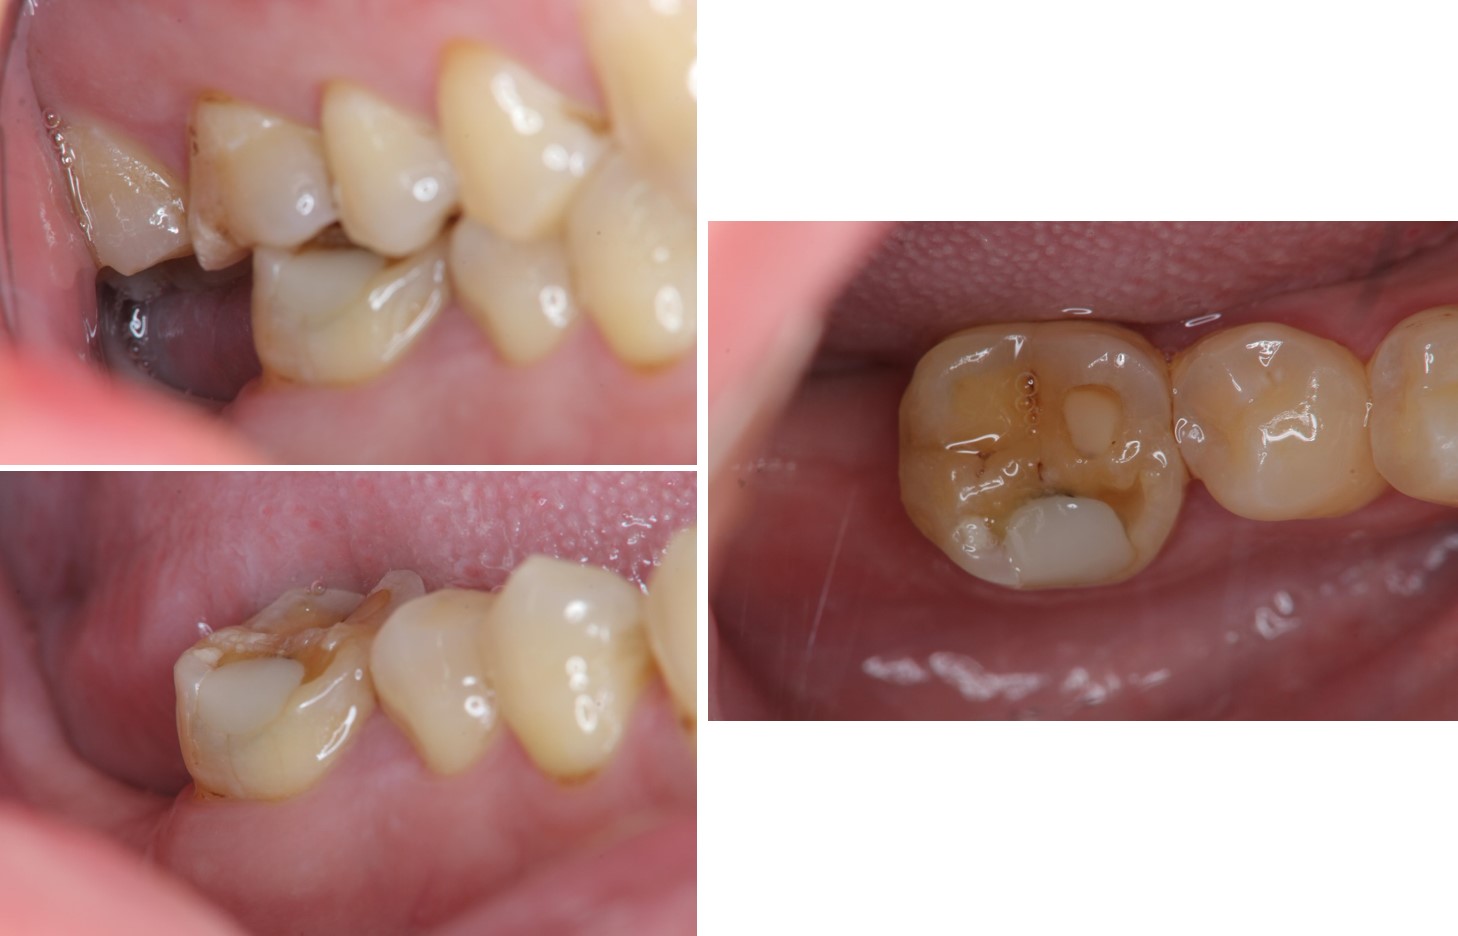

陶瓷冠蓋體-牙裂-#46(牙齒斷裂)

治療前,頰側牙齒斷裂